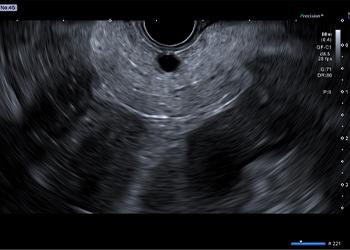

The Aplio i800 EUS ultrasound system’s innovative imaging technology provides clarity, depth, and detail. Clear imaging with high-resolution and deep penetration, as well as an abundance of imaging technologies, allow you to safely perform the procedure and diagnosis confidently.

- Differential THI (D-THI): Expands the effective bandwidth by transmitting a combined pulse with two different frequencies to simultaneously achieve increased penetration as well as high resolution with sensitivity in both superficial and deep regions compared to other THI methods.

- Full Focus: Enables clear, uniform images from near and to far field without the need for focus adjustments.